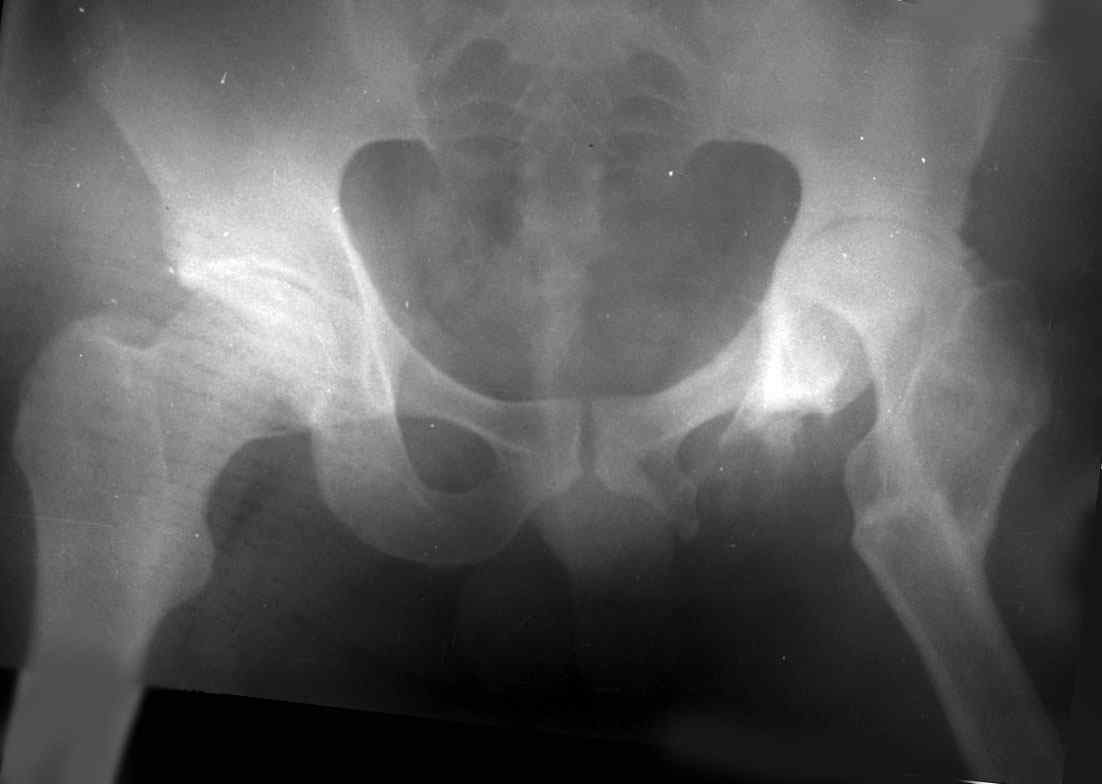

.........наверное не повезло. Но иногда это выход и очень хороший. М., 21 года спрыгнул в Армии с машины с исходом в гнойный коксит, свищевой формой в течении 1,5 лет. Операция проведена в 1988 году. результат хороший и сейчас и мы с пациентом хорошие приятели (Рентг-гр и фото прилагаю).

Еще один раз произведена реконструкция проксимального отдела юноше 17 лет с посл гематог остеомиелита тотальным дефектом проксимального отдела бедра и укорочением 16 см.(проксим отдел в виде "сосульки"). Произведена одноэтапная последовательная реконструкция, удлинение в с/з, затем в н/з. Рентгенограммы к сожалению утеряны.

Результат, поверьте, фантастический. Колено почти не пострадало. Сейчас сам удивляюсь, как хорошо получилось. РПО по Илизарову - Выход из ситуации иногда единственный, и хороший почти всегда, но трудоемкий для врача и тяжелый - пролонгированно для больного(в этом то и "собака порыта").